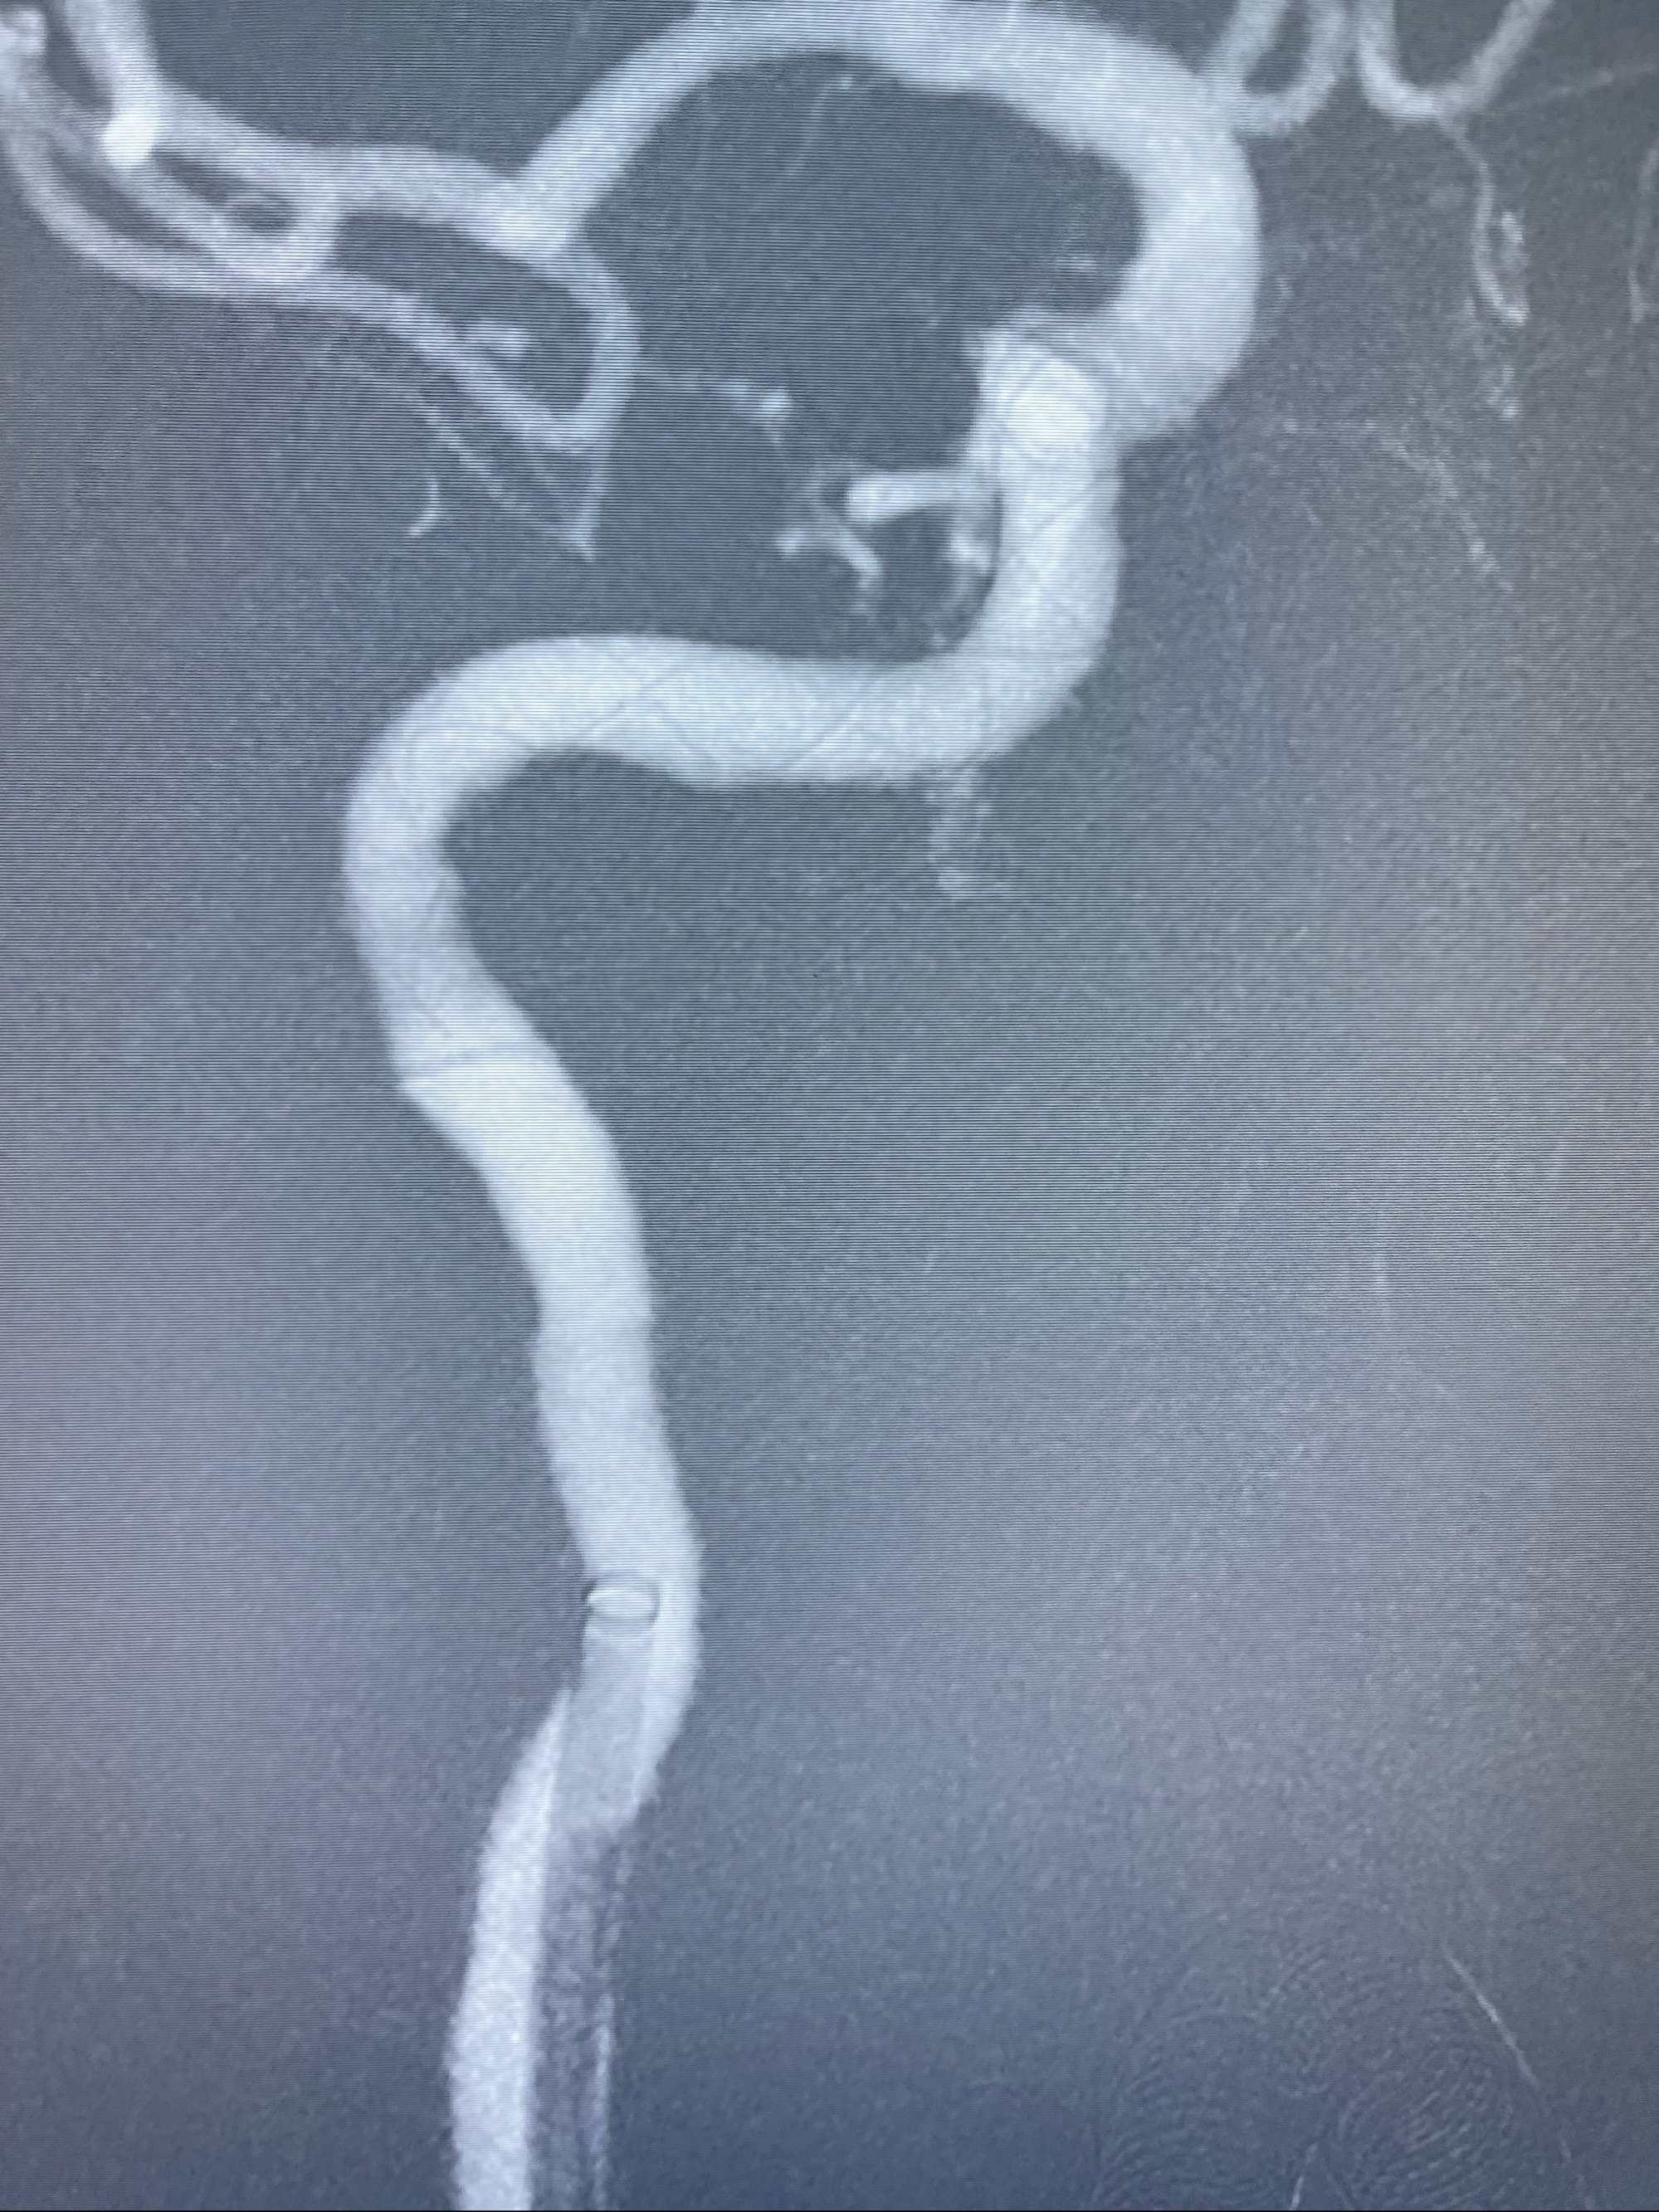

2023-07-10DSA:右侧颈内动脉岩骨段夹层伴中偏重度狭窄改变,左侧颈总动脉闭塞、右侧颈外动脉由右侧肋颈干甲颈干吻合代偿

箭头所示为颈内动脉岩骨段重度狭窄,结合MRI,考虑为肿瘤侵犯右侧颈内动脉

箭头以近至支架段管腔不规则狭窄